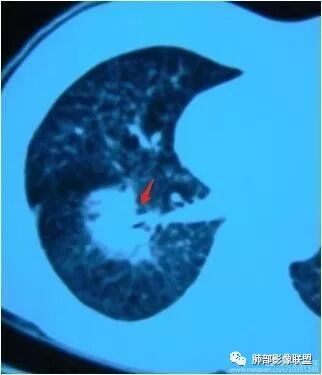

南边:糊墙,长轴与胸膜平行;边缘收缩+膨隆;脐凹征

常规:隐球菌与癌鉴别

脐凹征,高度提示恶性

南边老师论述:    分叶凹陷的地方有血管,支气管进去,这个价值很大,后来引申到血管、支气管从凹陷的地方进去就叫脐凹征,就像番茄柄🍅,辣椒柄、苹果柄🍎一样的。后来就把这个做为脐凹征,95%以上的特异性。如下例:

后来发现胸膜牵拉,由远端凹陷的地方进去,他的价值也很大,诊断腺癌,几乎很少失误,后来把这个也纳入到脐凹征里。由凹陷处进入的胸膜牵拉征,由凹陷处进去的血管,都属于脐凹征。原理是由凹陷处进去的血管,因为肿瘤膨胀生长,生长过程中遇到血管,支气管区域受阻,边缘代偿性生长,膨胀的更厉害了,所以局部凹陷,前提是血管、支气管肯定在肺门侧,不会在远端有一条血管阻碍他的,可能性太小了。

脐凹征,支气管、血管引起的在肺门侧,因肿瘤生长在近端膨胀受阻的,病灶本身围绕支气管、血管周围包绕的不算,只有进去其中受阻的才算。